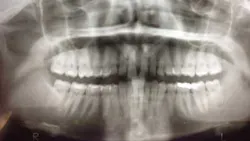

Early assessment for potential impaction is easily done by taking a panoramic radiograph at the age of 7. Ectopic positioning of canines may result in future impaction; if this is the case, then intervention can be initiated. Research has also shown that early removal of the deciduous canines can offer a favorable eruption pattern of permanent counterparts. (4,5) If crowding is present, then the arch can be expanded.

When a full permanent dentition is present (with the exception of impacted canines), the labial/palatal position of the canine will have an influence on what the provider can do. (1) Arguably, obtaining a CBCT is considered mandatory and will allow for a more inclusive treatment plan creation. If angulation is favorable, then consideration to remove the primary canine and wait six months to see if there is movement of the permanent canine is an option. If extraction of the canine(s) is needed, then a premolar substitution, which is dependent on occlusion, can be used in the space. An implant can also be an appropriate alternative. When pulling a canine into the occlusal arch, there is risk involved. Trauma to adjacent teeth (root resorption) and ankylosis are some of the most common complications.The patient was put in full orthodontics and referred to a surgeon for extraction of the primary canines, exposure, and placement of retention on the impacted canines to pull them directly down from their current position.